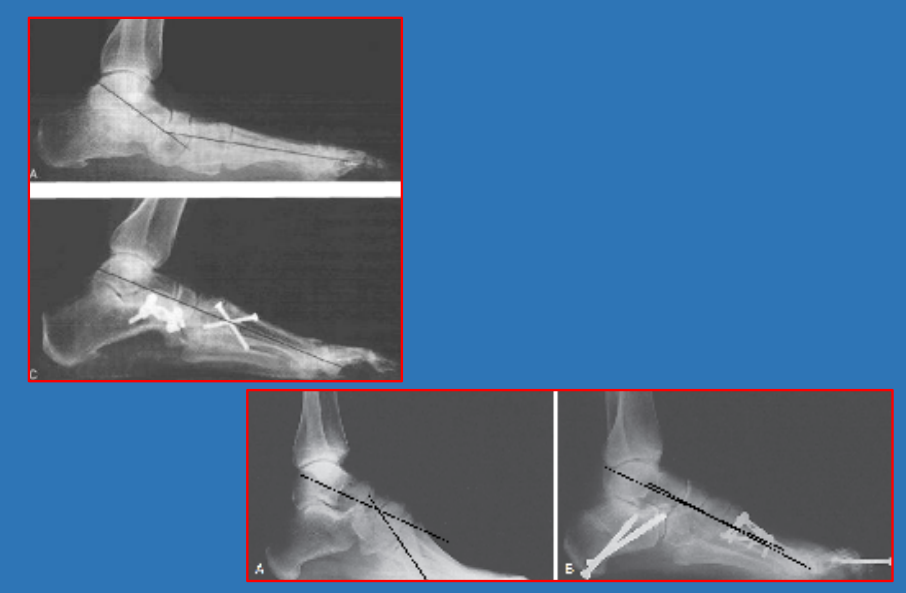

腓骨短缩测量

胫距角talocrural angle:通过在踝穴位X线片上测量内、外踝尖端连线与胫骨远端关节面平行线的夹角。正常值为8~15°,与健侧相差3°以上即表示有腓骨短缩。

19 前后足—侧位距骨第一跖骨角

—侧位距骨第一跖骨角lateral talo-first metatarsal angle,meary‘s angle:侧位X线片上距骨轴线和第一跖骨轴线的夹角。反映前足和后足的对线关系,常用来评价足内侧足弓畸形,其交点可用来确定中足塌陷的部位。

正常范围:±4°(交于跖侧为正)。应用广泛。

4~15°轻度平足

15~30°中度平足

>30°重度平足